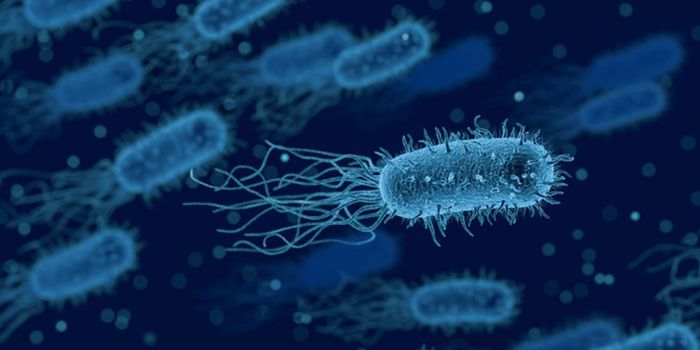

MAR 26, 2024MicrobiologyThere are trillions of microbes in the human gastrointestinal tract, each of which expresses its own genome, and carries ...

FEB 02, 2024Clinical & Molecular DXEscherichia coli is a microbe that is a natural resident of the gastrointestinal tract. Some strains of this microbe can ...